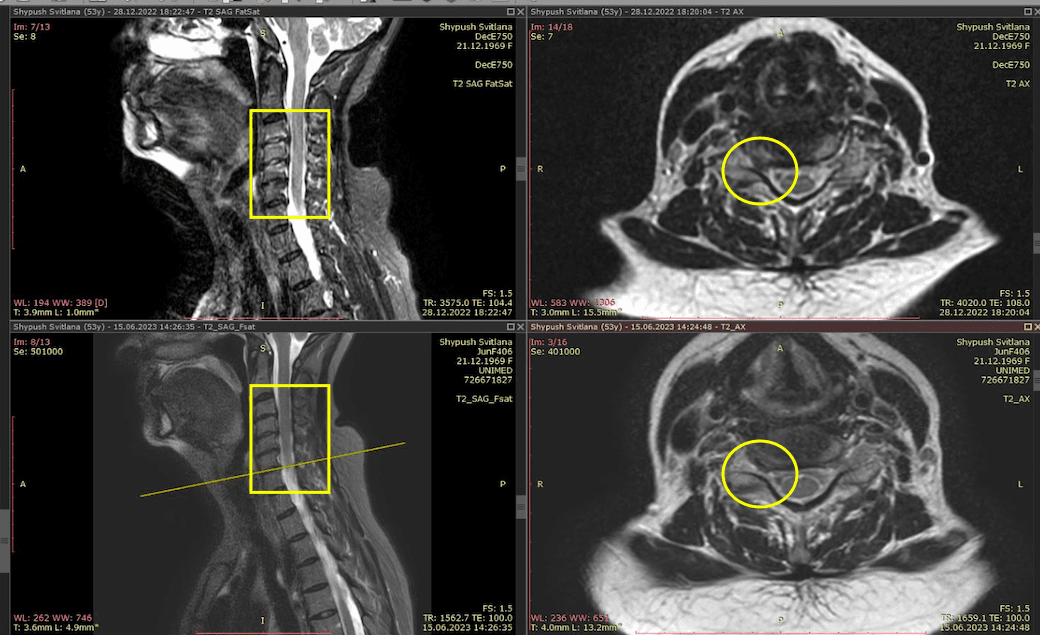

Метод лікування грижі шляхом стимуляції резорбції в Україні був впроваджений у 2020-2021 роках.  Алгоритм оцінки грижі на предмет резорбції, що використовується у клініках – є авторським, розроблений лікарем Боханом А.Ю.